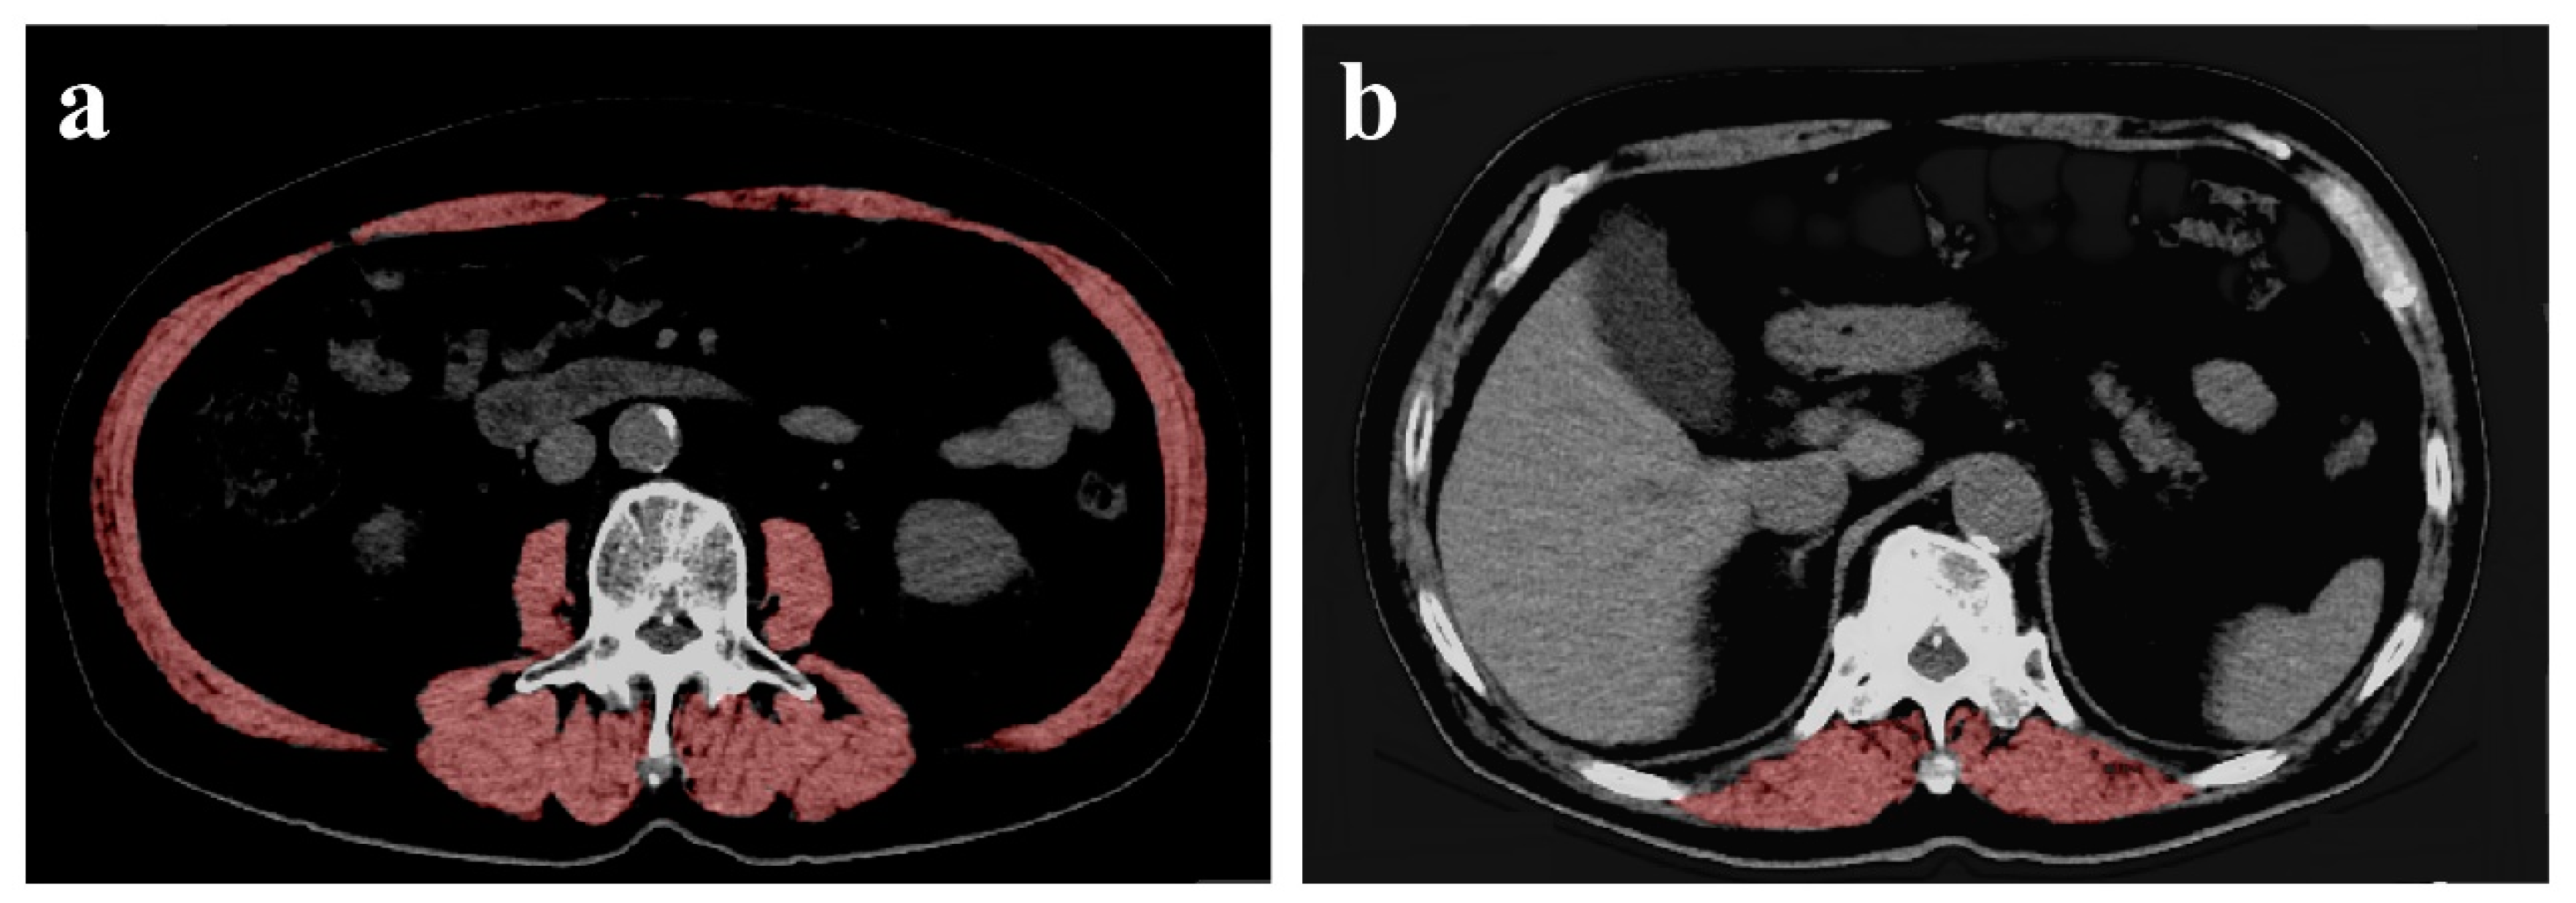

2.3. Measurement of CSA of the Muscles